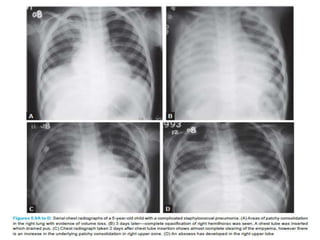

Staphylococcal pneumonia showing

bilateral patchy opacities

pneumatocele formation in a right lower lobe

consolidation due to staphylococcal

pneumonia

multiple residual

pneumatoceles

following

an episode

of

staphylococcal

BACTERIAL PNEUMONIAS Staphylococcal Pneumonia •Staphylococcusaureus (casues marked destruction and abscess formation) •community acquired, particularly in infants and elderly individuals, often complicating influenza • bronchopneumonic pattern, initially involving the lower zones consolidation spread rapidly -> become confluent, resembling lobar pneumonia. Volume loss, early and large effusions, empyema and abscess formation are common Resolution is slower with residual fibrosis Staphylococcal pneumonia showing bilateral patchy opacities

pneumatocele formation ina right lower lobe consolidation due to staphylococcal pneumonia multiple residual pneumatoceles following an episode of staphylococcal pneumonia